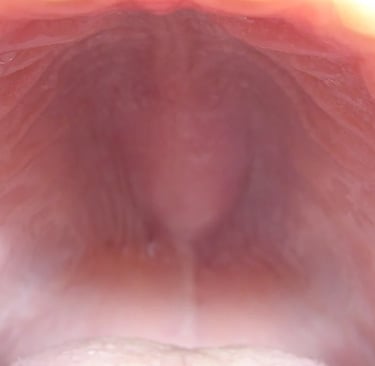

Understanding Palatal Tori

Palatal tori can vary significantly in size, shape, and location. While they are typically harmless, their presence can complicate the fit of clear aligners. According to a study published in the American Journal of Orthodontics and Dentofacial Orthopedics, around 20% of the population may present with some form of palatal tori, making it a relevant consideration for orthodontists.